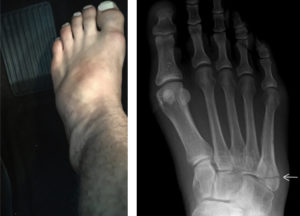

Если говорить о симптомах, то они будут характерными для всех переломов: болевой синдром, нарушение движения; если человек двигается – боль становится сильнее; кровоизлияние, опухание.

Однако после того, как пациент будет внимательно обследован, обнаружатся признаки, свидетельствующие о травме именно этого участка:

- острые болевые ощущения при ощупывании соответствуют локализации данной кости;

- можно отметить, что ее контуры деформированы;

- боль становится сильнее, если надавливать на 4-5 плюсневые кости, если пробовать отводить переднюю часть ступни, если поворачивать стопу.